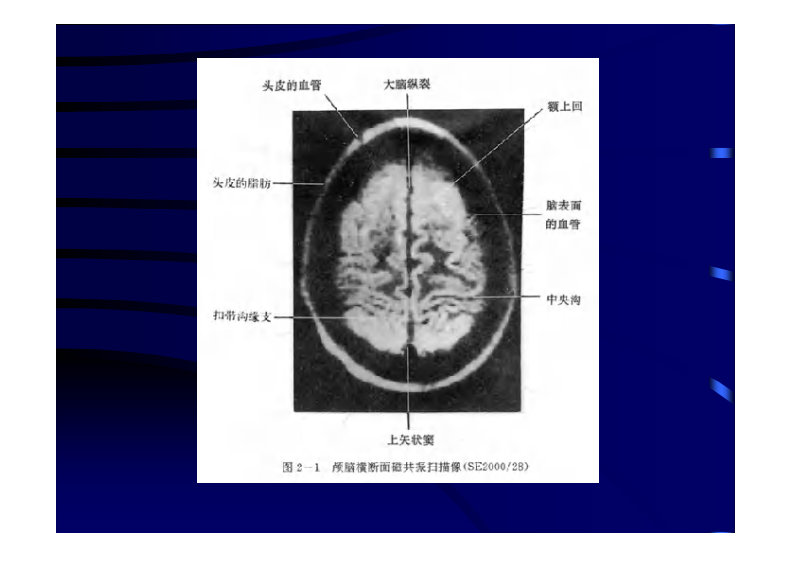

颅脑CT、MRI.pdf